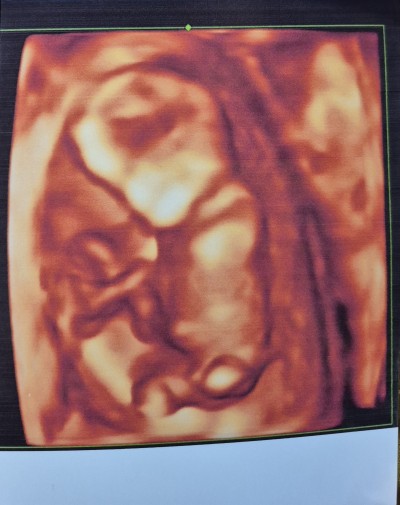

13 hafta 4 gunluk sizce cinsiyet nedir anlayan varmi doktor bi tahminde bulundu ama hafta erken oldugu icin kesinlik vermedi.

Gebelik haftası 13+4

erkek gibbiiii

Erkek gibi baya belli ama

Valla canm bende erkek olarak gördüm orasına doğru bakın sizde fark edeceksiniz kız erkek fark etmiyor gerçekten sağlıkla gelsinler 👣❤️

Net erkek bence hayırlısı olsun